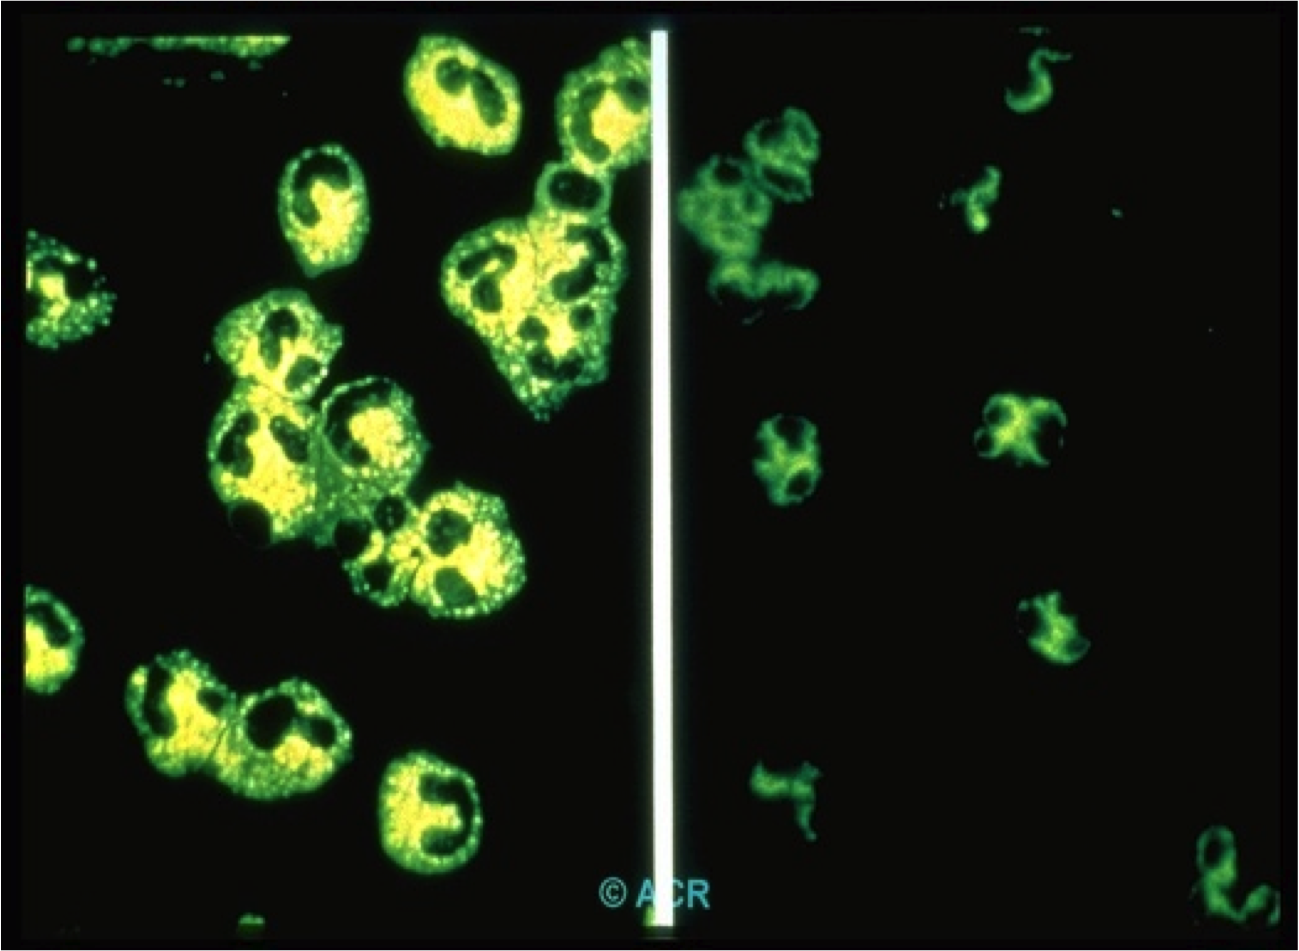

35 yo man is seen with eye inflammation [see image here], sinusitis, lung lesions, hemoproteinuria and gangrene of the fingers.

SMALL VESSEL VASCULITIS

ANCA